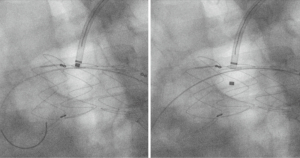

Parallel stent grafting in the aortic arch carries similar concerns for complications compared to open surgical repair including stroke, need for secondary interventions, and operative mortality. What is unique with parallel stent grafting is the planned disruption of the proximal seal zone of a TEVAR device. Creation of such gutters between the TEVAR device, the parallel stent graft and the aortic wall are the Achilles heel of this technique. These gutters represent Type 1A or 1B endoleaks that if persistent can lead to systemic arterial pressure within the aneurysm sac increasing the risk of aneurysm rupture. The risk of Type 1 endoleak is reported to be as high as 23% in midterm follow-up (13) (Figure 4).

Lindblad et al. reported a meta-analysis of parallel grafts in abdominal and thoracic aortic stent grafting and included a review of those involving the aortic arch (14). They found 17 series and 23 case reports involving 314 patients who underwent parallel grafting of the supra-aortic trunks. Ninety-eight of the reported cases were in emergent situations. Early parallel graft patency was 99% with endoleak reported in 33 patients (11%). Thirty-day mortality occurred in 14 patients (4%) and procedure related complications were reported in 20 patients (6%). Fifteen (45%) thoracic arch Type 1 endoleaks were observed and seven were reported to seal. Nine (27%) thoracic endoleaks were embolized or glued and five were treated by extension of the thoracic endograft. Three thoracic cases required open conversion, all for Type 1 endoleak.